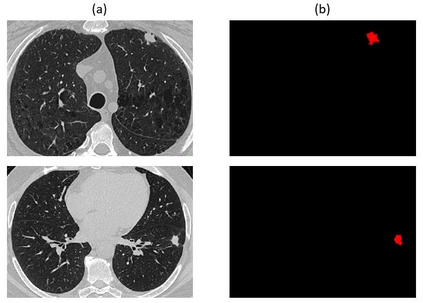

Non-small cell lung cancer (NSCLC) is a serious disease and has a high recurrence rate after the surgery. Recently, many machine learning methods have been proposed for recurrence prediction. The methods using gene data have high prediction accuracy but require high cost. Although the radiomics signatures using only CT image are not expensive, its accuracy is relatively low. In this paper, we propose a genotype-guided radiomics method (GGR) for obtaining high prediction accuracy with low cost. We used a public radiogenomics dataset of NSCLC, which includes CT images and gene data. The proposed method is a two-step method, which consists of two models. The first model is a gene estimation model, which is used to estimate the gene expression from radiomics features and deep features extracted from computer tomography (CT) image. The second model is used to predict the recurrence using the estimated gene expression data. The proposed GGR method designed based on hybrid features which is combination of handcrafted-based and deep learning-based. The experiments demonstrated that the prediction accuracy can be improved significantly from 78.61% (existing radiomics method) and 79.14% (deep learning method) to 83.28% by the proposed GGR.